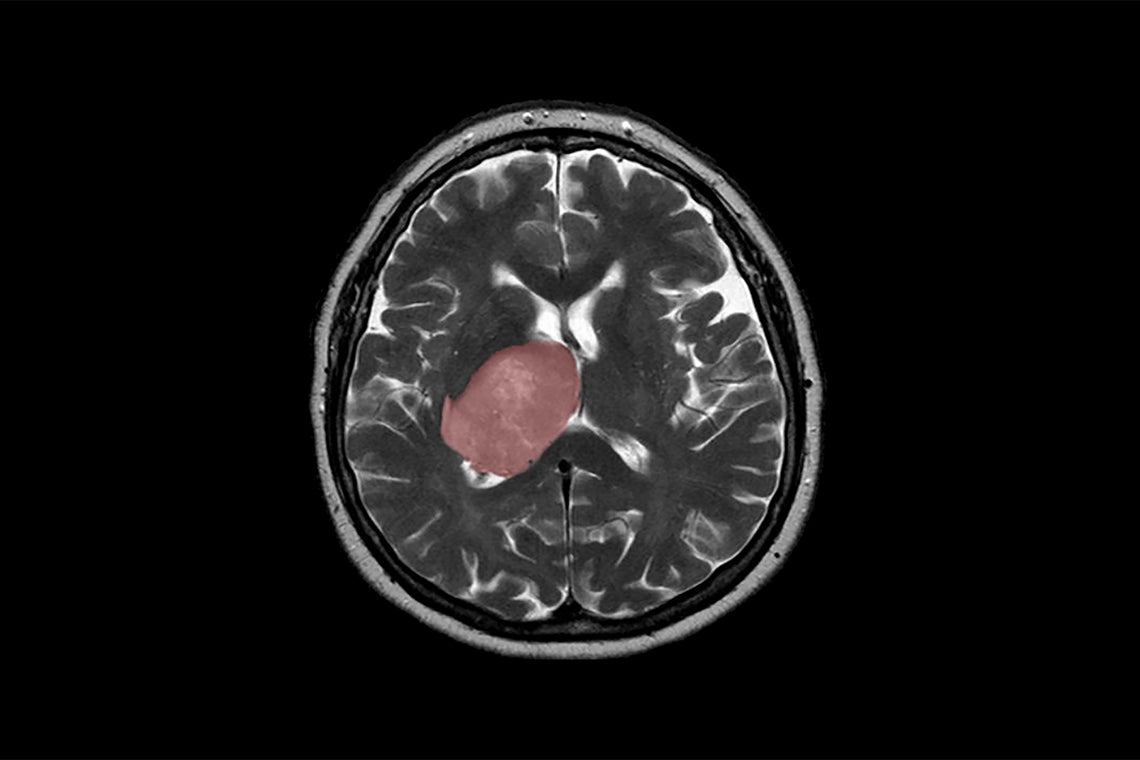

A brain scan shows a glioblastoma tumour highlighted in red (photo by Hellerhoff via Wikimedia Commons)

The healing process that follows a brain injury – from trauma to infection and stroke – could spur tumour growth.